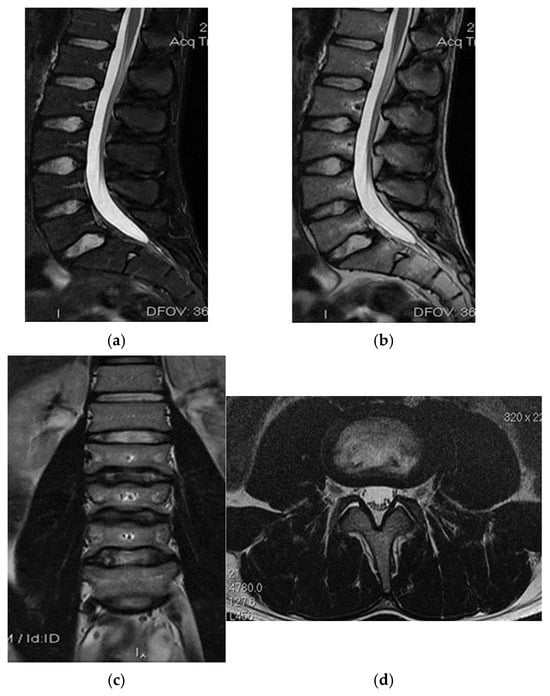

In the second case, the patient, a left back, experienced pain in the inguinal region and left thigh while running during a national team training session. This 23-year-old national team member has six years of experience as a first-league professional in Romania, standing 202 cm tall and weighing 105 kg. Pelvic radiography was incorrectly performed (incorrectly) and the patient was diagnosed with left thigh muscle damage. (Figure 4).

Figure 4.

Incorrect pelvic X-ray.

Three years post-trauma, the player develops symptoms of peripheral neuropathy with sensory and motor symptoms in the external popliteal sciatic nerve. Lumbar degenerative disc disorder or piriformis syndrome was suspected, and lumbar and pelvic MRI was performed.

The spinal MRI revealed no evidence of degenerative lumbar disc pathology or radiculopathy (Figure 5). Magnetic resonance imaging (MRI) and radiographic examination of the pelvis revealed an old avulsion injury with a detached bone fragment at the insertion site on the left ischial tuberosity, involving the semitendinosus, semimembranosus, and biceps femoris muscles (collectively referred to as the ischium-calf muscles). This condition has led to the development of pseudoarthrosis and bone edema at the level of the ischial tuberosity. The sciatic nerve is positioned tangentially to the inflammatory response. Despite the detachment, the bone fragment remains vascularized due to the maintained insertion of the ischial calf muscles, preventing it from becoming a bone splinter (Figure 6 and Figure 7).

Figure 5.

(a) Spinal MRI: sagittal T2 fat sat acquisition, (b) spinal MRI: sagittal T2 acquisition, (c) spinal MRI: coronal T2 acquisition, (d) spinal MRI: axial T2 acquisition.

Figure 6.

(a) Pelvic MRI: coronal stir acquisition, (b) pelvic MRI: sagittal PD fat sat acquisition, (c) pelvic MRI: sagittal PD fat sat acquisition, (d) axial stir acquisition, (e) axial stir acquisition, (f) axial T1 acquisition.

Figure 7.

(a) Pelvic X-ray—ischial tuberosity, (b) ischial tuberosity X-ray—detail.

The pseudoarthritis secondary to the old ischial tuberosity avulsion can be visualized as follows:

- -

- An old detached bone fragment with signal in the T1 and T2 ponderations, similar to the rest of the existing bone structures, but showing focal alterations of the PD fat sac and STIR hypersignal, indicating bone edema.

- Fluid accumulation in T2 hypersignal, T1 hyposignal, between the torn bone fragment and the remaining tuberosity

- The altered PD fat sac hypersignal in the sciatic nerve, adjacent to the inflammatory process, indicates changes suggestive of focal neuritis.